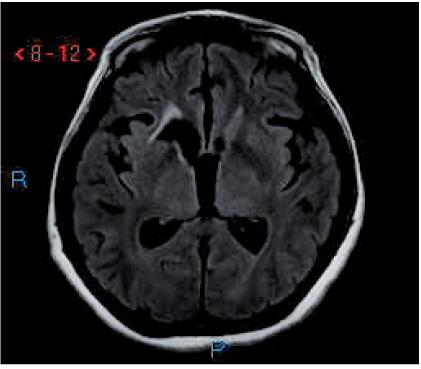

新型隐球菌感染的同时性中枢神经系统并发症。

Simultaneous central nervous system complications of C. neoformans infection.

The most common neurological manifestation of Cryptococcus neoformans infection is meningitis. Other less common manifestations include parenchymal central nervous system (CNS) granulomatous disease, hydrocephalus and stroke. C. neoformans is often suspected in immunodepressed patients, but it can be easily overlooked in otherwise healthy patients. This paper provides a detailed clinical description of a patient without immunosupression who developed multiple simultaneous neurological manifestations after the infection with C. neoformans.

新型隐球菌感染最常见的神经学表现是脑膜炎。其他较不常见的表现包括实质性中枢神经系统(CNS)肉芽肿病、脑积水和中风。新型隐球菌感染常被怀疑发生于免疫抑制患者,但在其他方面健康的患者中也很容易被忽视。本文详细描述了一名无免疫抑制的患者,该患者在感染新型隐球菌后同时出现了多种神经学表现。